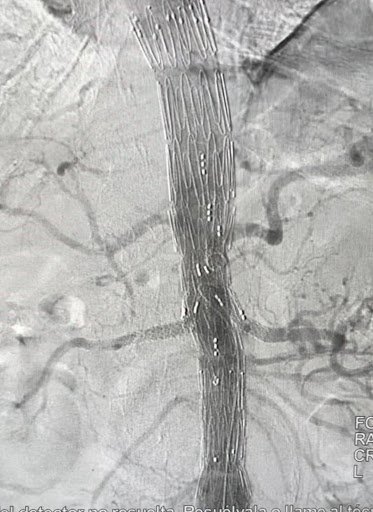

Post-treatment: Endovascular reconstruction with stent placement

Post-treatment

Endovascular reconstruction with stent placement. Restoration of venous flow with symptom resolution.